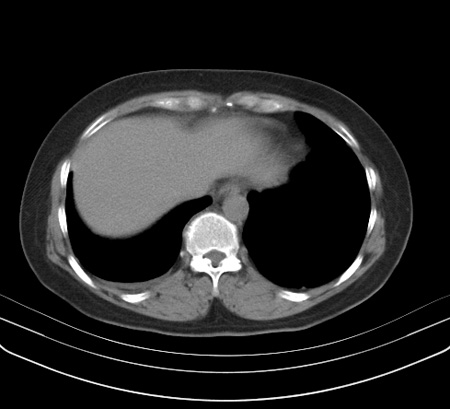

以下是引用余辉在2009-2-19 20:10:00的发言:[br]多考虑急性感染性病变,右中叶尚可见多枚小斑片状影,多为化脓性肺炎,双侧胸腔积液

以下是引用随光逐影在2009-2-19 20:33:00的发言:[br]1)考虑右肺炎症;建议抗炎治疗后复查。2)双侧胸腔积液(以右侧为甚)。

以下是引用花凤凰在2009-2-19 20:46:00的发言:[br]病人有发热,胸痛急性起病,主要病变位于右肺中叶外侧段,呈楔行改变,位于外带胸膜下,考虑为肺梗塞可能!!!!!!!!!!!!!!!!!!!!!!!!!!!!!!!!!!!